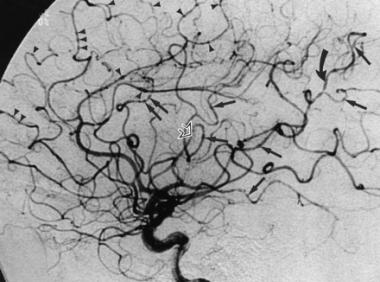

Cerebral digital subtraction angiography (DSA)

- Cerebral DSA has long been regarded as the gold standard in terms of definition and accuracy but involves an invasive catheter-based procedure with a small but real risk of vascular damage and usually quoted 1% risk of stroke. Death is seen in 1 in 1000. It is done in the cath lab and takes 20-30 minutes.

- Vascular access is gained via the femoral artery (radial artery is gaining more popularity nowadays) under local anaesthesia by an interventional neuroradiologist and the catheter is passed into the origins of the cerebral vessels (carotid and vertebral) and about 5 ml of contrast injected and a cine film is taken. Image manipulation can remove the bone and gives an excellent view of vessel anatomy and pathology.

- DSA is the imaging of choice when there is a likely treatment gain to be considered such as pre-operational investigation of an AVM or Aneurysm or suspected Vasculitis where the benefits of accurate diagnosis outweigh the risks. DSA isn't always needed as CTA can actually be better than DSA for looking at aneurysms.

Vasculitis | Beading of arteries due to narrowing and dilation. Primary angiitis may involve small vessels |

Takaysasu's | As for vasculitis plus formation of anastomoses with the cloud of smoke appearance |

Causes of Beading

- Cerebral vasculitis

- Tumour embolisation

- Radiation damage

- Meningitis/Chronic meningitis

- Cocaine, Amphetamines

- RCVS

- Malignant Intravascular lymphoma

- Fabry's disease

- Phaeochromocytoma